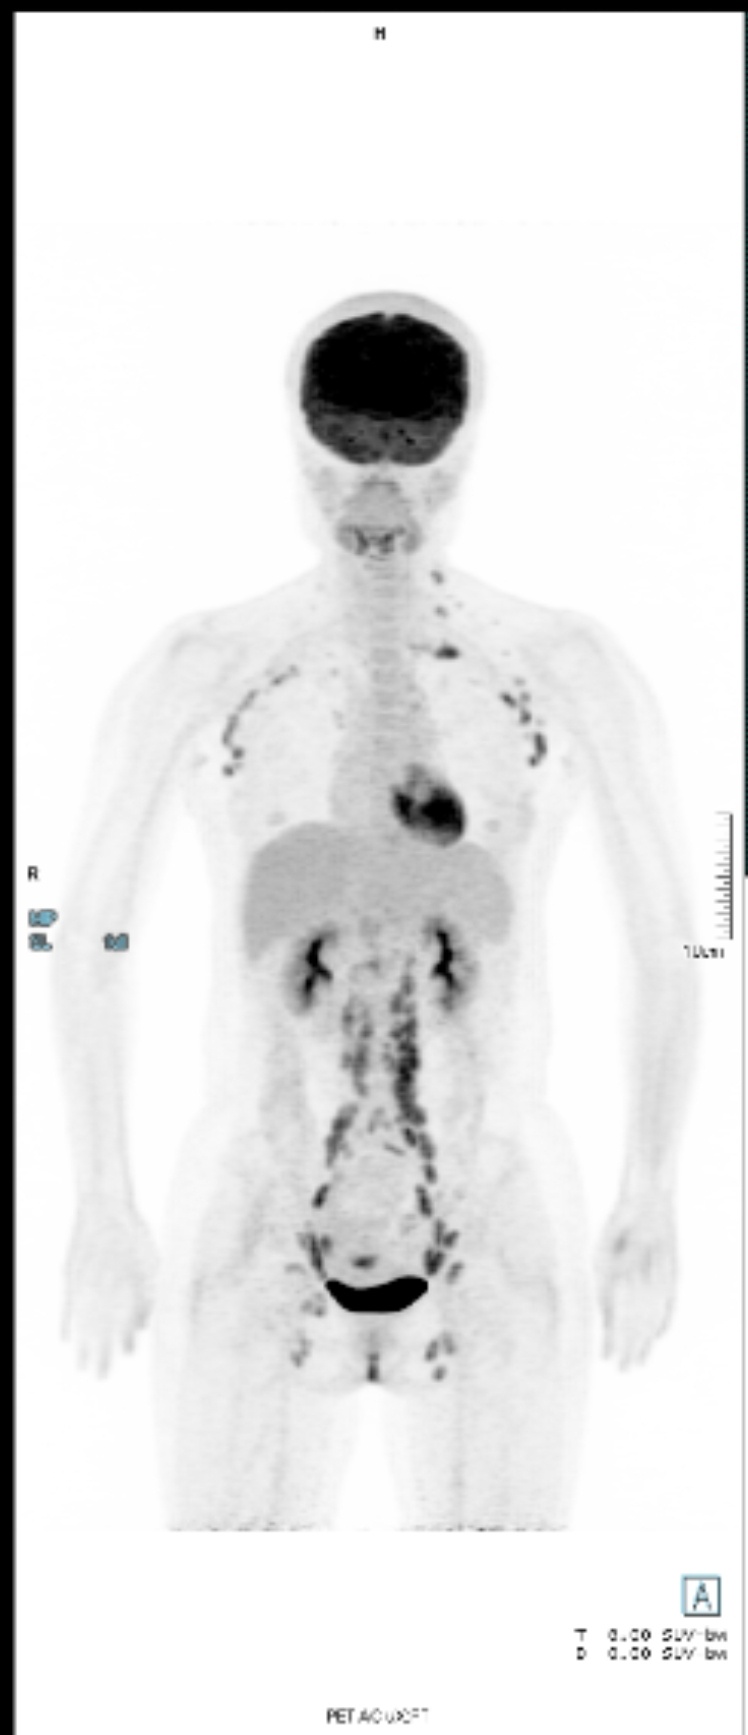

滤泡淋巴瘤治疗指征包括:①存在大肿块(肿块直径≥7cm、3个明显的淋巴结区每个均≥3cm、脾增大、腹水或胸腔积液);②出现发热、盗汗、消瘦症状;③血细胞减少(白细胞<1.0×10^9/L和/或血小板<100×10^9/L);④白血病(恶性细胞>5.0×10^9/L)⑥危及终末器官(如心脏、肾脏等)功能;⑦在6个月内病情稳定的或快速的进展。你看看有没有骨累及

1~6条我都没有,第七条说不清楚,每三个月都是只做浅表淋巴结B超和腹部B超,浅淋巴结是这三年范围慢慢变大的,腹部B超一直正常,去年8月份做过一个腹部CT平扫,就写了髂血管腹股沟淋巴结轻度增大,尺寸都没写。 |